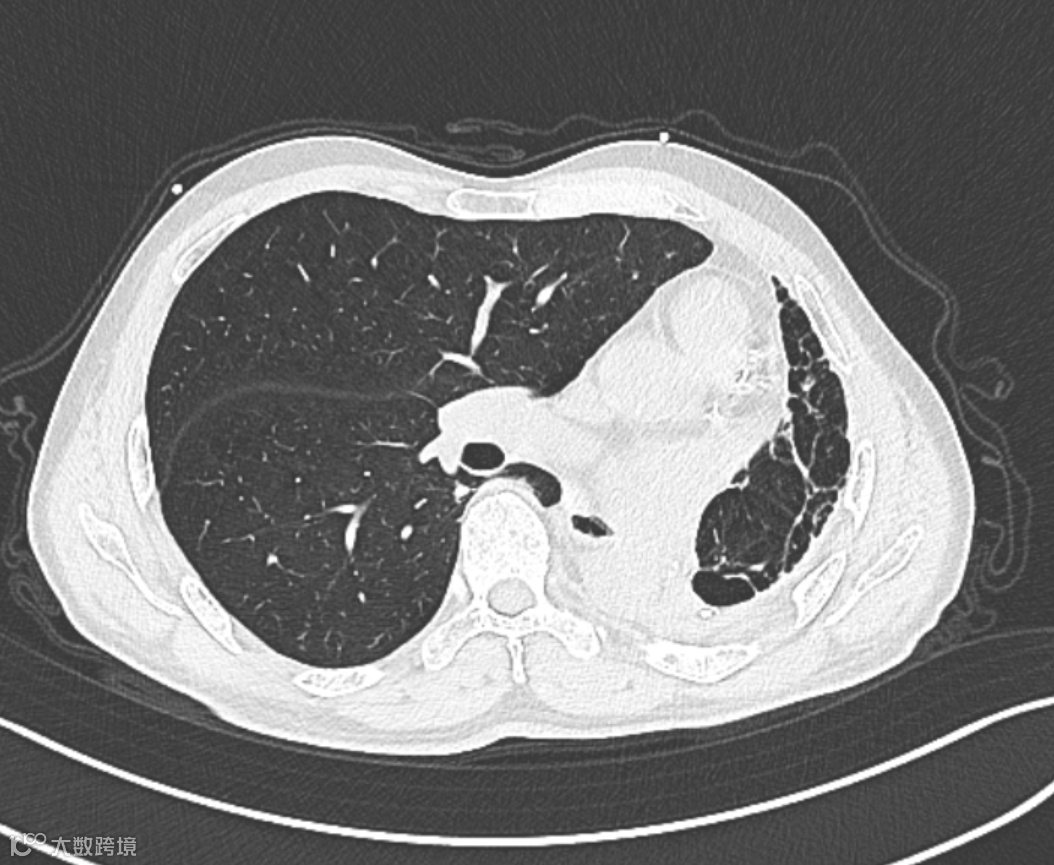

检查所见:患者接受左下肺切除术后,残余肺组织以左肺上叶尖段为主,伴右肺代偿性过度膨胀及形态结构改变。右肺上叶前段可见一实性结节,大小约13.6mm×11.5mm,边界尚清,密度欠均,边缘呈浅分叶状。余右肺散在少许条索影及肺气肿表现。

▲▲▲右肺代偿性过度膨胀